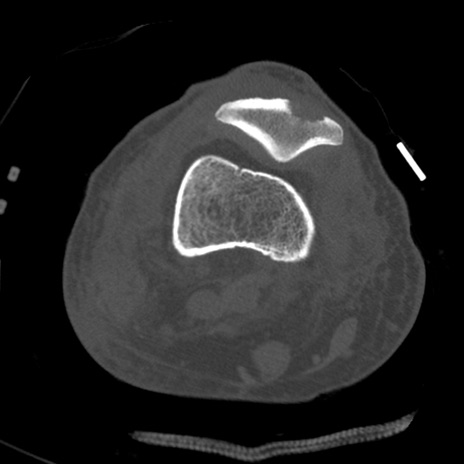

症例28 右膝関節CT(横断像)

右膝関節CT